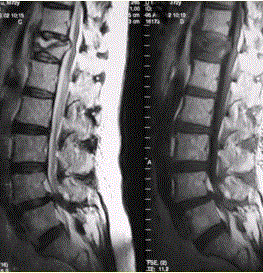

问题 患者男,70岁,因肝癌入院,准备行肝移植手术。住院期间因腰扭伤而腰痛,故行腰椎MRI检查(如下图)。 观察上面的影像后,你认为正确的是

选项 A.基本可以明确T12椎体为骨质疏松性压缩性骨折 B.基本可以明确T12椎体为转移瘤 C.必需再行CT检查,观察有无骨质破坏 D.DWI序列可以进一步提供鉴别椎体良恶性骨折的有价值信息 E.必须再进行MRI增强检查 F.必须再进行CT增强检查

答案 AD